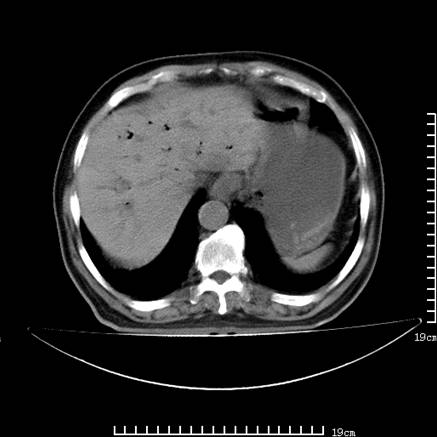

以下是引用zsl6918在2008-7-19 21:53:00的发言:[br]胆总管结石并胆系感染,胆囊切除术后改变。

以下是引用sch2008在2008-7-19 22:03:00的发言:[br]肝内胆管及胆总管积气,并胆总管结石,考虑;胆囊切除术后,胆系感染

以下是引用xinliheng001在2008-7-19 21:59:00的发言:[br]胰头段胆管结石肝内外胆管扩张积气。

以下是引用liaoqiang在2008-7-19 22:26:00的发言:[br]胆总管结石伴胆系感染。